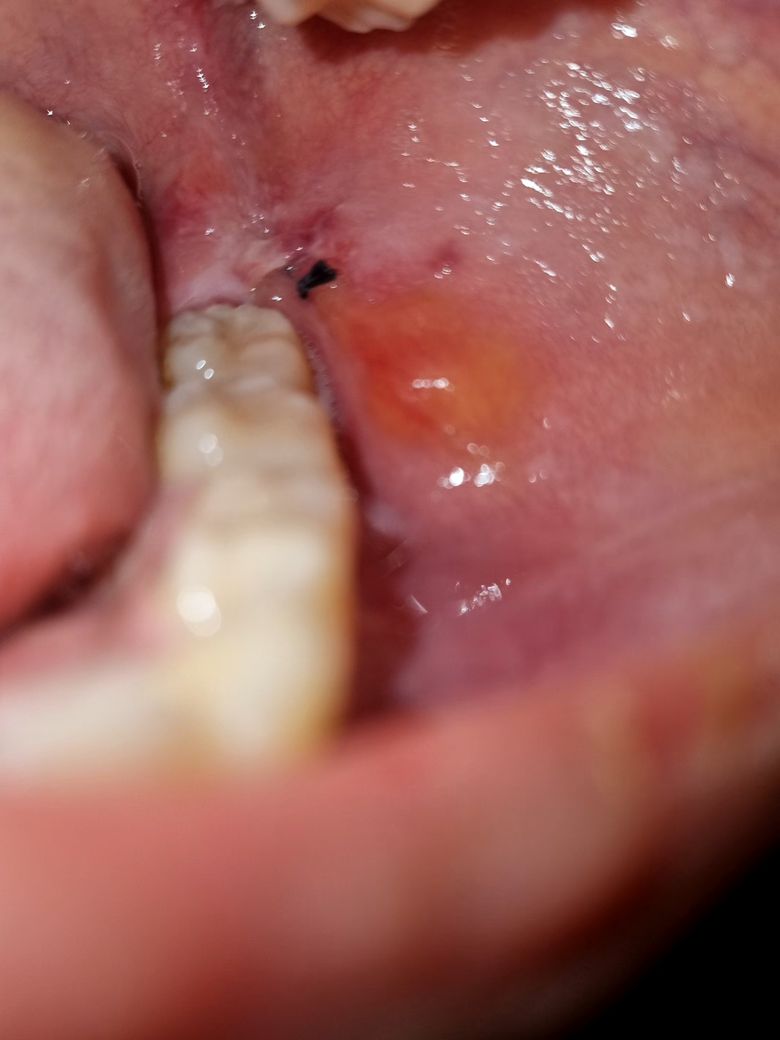

사랑니 발치 후 볼 안쪽 튀어나옴. 오른쪽은 괜찮은데 왼쪽만.

사랑니 발치 후 오른쪽은 붓기가 괜찮은데 왼쪽은 계속 붓고 있고 볼 안쪽에도 뭔가 튀어나왔네요.

• 1번 째 사진

• 2번 째 사진